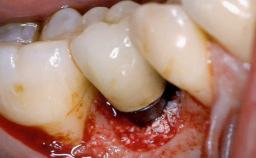

Due to their promising clinical performance, zirconia implants have recently become popular alternatives to titanium implants, particularly for areas with high esthetic demands (Holländer and coworkers 2016; Roehling and coworkers 2016; Lorenz and coworkers 2019). However, regardless of the reported high survival and success rates, zirconia implants were affected by peri-implant diseases over the short observation period, suggesting the importance of treating peri-implant diseases at zirconia implants (Becker and coworkers 2017). In their case, Frank Schwarz and Ausra Ramanauskaite present 3-year results following mechanical debridement alongside Er:YAG laser monotherapy.